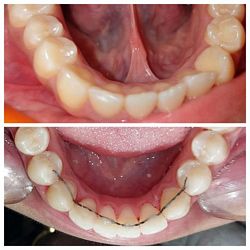

Case No: 12

Malocclusion Type: Crowding in Maxillary and Mandibular Anteriors

Mechanics: Anterior Crowding Relieved by Distalization of Mandibular Posteriors

Intra-oral : Pre-treatment : Occlusal View

Intra-oral : Post-treatment : Occlusal View